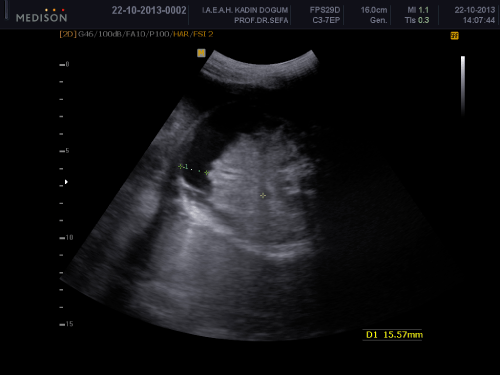

A 34-year-old woman, gravity 2, parity 0, abortion 1 is referred to our clinic at 32 weeks of gestation because of fetal intraabdominal cystic formation. She had an unremarkable prenatal course until this week. In history, she had no clinical significant coincident disease. We learned that she attended all prenatal visits regularly and she had no pathological finding in all previous visits. In the 32 weeks ultrasonography fetal biometric measurements were compatible with gestational age, amniotic fluid volume was in normal limits. Maternal blood pressure was 110/70mmHg and fetal movements were well. In ultrasonography, we detected a 15mm spheric cystic formation on the left lower side of fetal abdomen (Figure 1). The cystic formation was not related with renal structures and bladder. In Doppler sonography, we did not determine intracystic blood supply. Bilateral renal structures were evaluated normal, fetal intestines were observed normal. Because the fetus is female, cystic formation was anechoic and fetus had no accompanying genitourinary or gastrointestinal abnormalities we primarily suggested on an ovarian cyst. Due to existing fetal ovarian cyst, patient was evaluated about maternal diabetes and hypothyroidism again and resulted both in normal limits. Patient was called for a new visit two weeks later. In the 34 th week, ultrasonography fetal growth was compatible with 34 weeks gestation and amniotic fluid was in normal limits again. Only abdominal circumference was measured as 99% for this week because of fetal intraabdominal fluid. In fetal abdomen, a widespread fluid accumulation was observed (Figure 2). Ovarian cyst on the left fetal ovary was regressed and was measured 14 mm with an ellipsoid shape (Figure 3). Intestines were floating in this fluid. Fetal thorax was normal and hydrothorax was not determined. We did not observe edema in subcutaneous tissue and we evaluated as primary fetal ascites even so we performed an assessment about hydrops fetalis. Hemogram, HbA1c, VDRL, TORCH screening, Parvovirus B-19 screening, indirect coombs test and anticardiolipin IgM and IgG studies were performed. Middle cerebral artery peak systolic velcity was 55cm/sec(1,12 MOM) and was not signifying fetal anemia. We recommended fetal karyotyping to patient because it could be an onset of fetal hydrops. However, patient did not accept karyotyping. All screenings were evaluated normal. Fetal cardiac examination was normal. Patient was called for a visit two weeks later again. At the next examination in the 36th weeks of pregnancy, fetal ultrasonography was completely normal. We have not observed any fetal ovarian cyst and fluid in fetal abdomen was completely regressed. Patient had a 3400 gr healthy baby on the 40th weeks of her pregnancy. No abnormal finding determined in postnatal abdominal ultrasonography.

Figure 2: idesread uid accumulation in etal adomen.